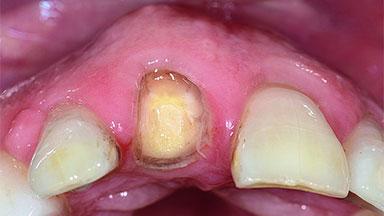

A 49-year-old female patient was referred for implant therapy to replace the upper right central incisor (tooth 11). The tooth had been assessed by an endodontist who diagnosed a vertical fracture of the root. The tooth had a hopeless prognosis and needed to be extracted. The patient was healthy and was not taking any medications. She was allergic to penicillin. The patient had high esthetic demands but her expectations were realistic. The extraoral examination revealed no facial asymmetries. The right temporomandibular joint demonstrated an opening click but was otherwise asymptomatic. The lip line was high with a significant gingival display.

Width of Edentulous Span 1 tooth (>= 7 mm) 1 tooth (< 7 mm) 2 teeth or more

Soft Tissue Anatomy Intact Defective

Soft Tissue Contour and Volume Ideal